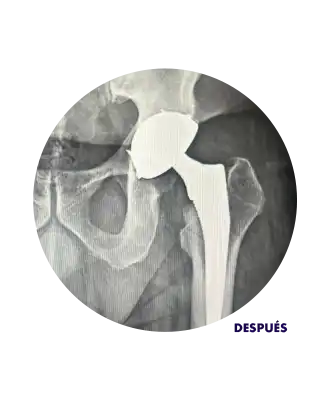

Reemplazo de Cadera

Reemplazo de Cadera con el Dr. Raúl López Solís

¿Qué tipo de prótesis se usan en un reemplazo de cadera?

Reemplazo de cadera: Cómo es y tiempos de recuperación.